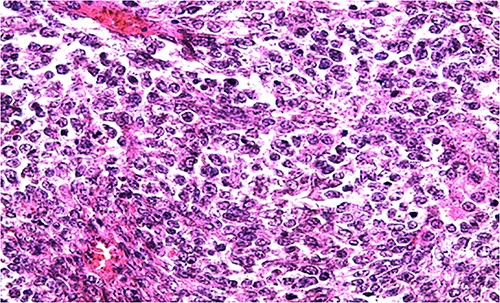

Biologically, the CA 125 tumor marker was at 126.2 IU/ml. The patient underwent a left adnexectomy and an omentectomy (small omentum). Macroscopically, the ovarian mass was smooth on the surface and fleshy on section with the presence of necrotic and hemorrhagic changes. On the histological level, the tumoral proliferation presents a diffuse architecture formed by sheets and clusters separated by fine fibrous septa. Tumor cells are rounded, small, and monomorphic with hyperchromatic, finely nucleolated nuclei and reduced cytoplasm. Mitotic activity is high (36 mitoses/10 HPF) (Figs 3 and 4). The samples taken from the small omentum were tumorous. An immunohistochemical study was carried out and showed diffuse positive expression by tumor cells of Vimentin, and focal by antibodies (Cytokeratin AE1/AE3, EMA, CD99, WT1, Inhibin, and SALL4) and an absence of expression by antibodies (CD45, Chromogranin, PAX8, and AFP) (Figs 5–7).

IHC: tumor cells show a nuclear strong expression of p16 (x400).